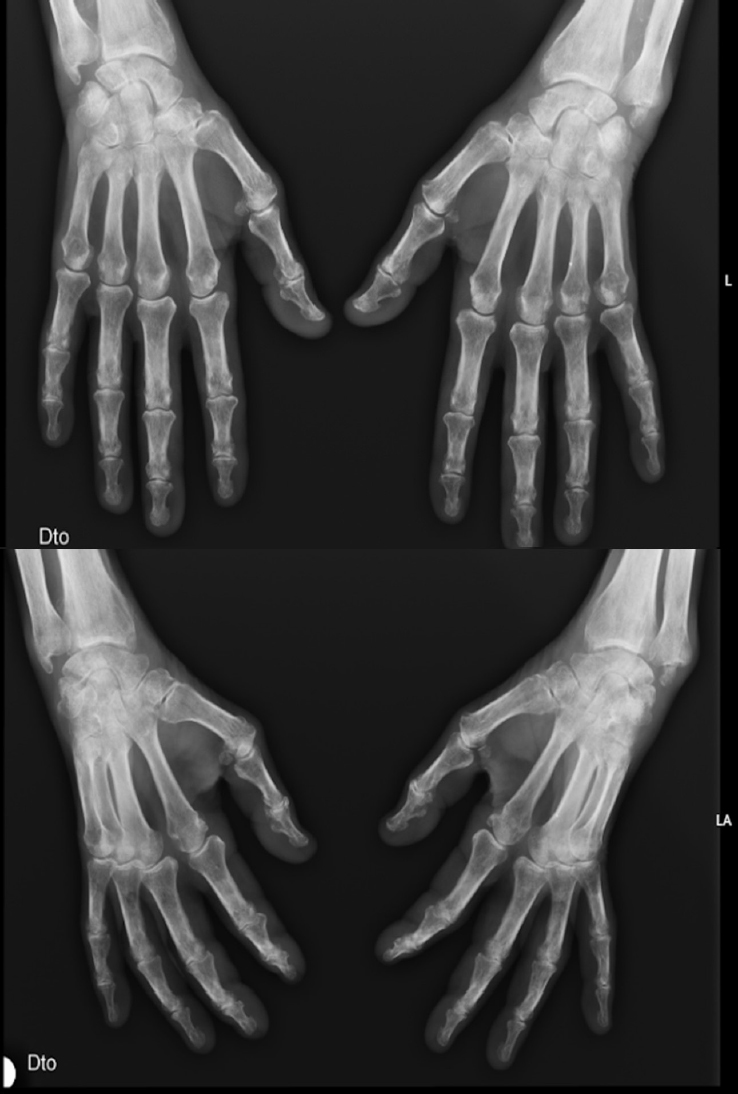

A 76-year-old man with hypertension and hypothyroidism went to the Emergency Department (ED) due to a 3-months history of weight loss (15% of the total body weight), asthenia and 1-hour morning stiffness. He reported no fever or night sweats. General examination revealed poor tolerance to any activity, severe muscle mass loss was evident; Body mass index (BMI) was 19.1 kg/m2. Several joints were painful, with symmetrical synovitis of the knees, elbows, wrists, proximal interphalangeal and metacarpophalangeal joints (Figure 1 demonstrate the impairment to the hand’s joints). Blood levels revealed inflammatory anemia (Hemoglogin 7.6 g/dL, reference range 12–15) and high inflammatory biomarkers (Erythrocyte sedimentation rate 96 mm/h, reference range 0–25; C-reactive protein 97.7 mg/dL, reference range 0–5; ferritin 757 μg/L, reference range 2.2–178). Blood and urine cultures were negative, and human immunodeficiency, B/C hepatitis viruses and syphilis serologies were negative too. Thyroid function were normal. Transthoracic echocardiogram excluded endocarditis. Full body computed tomography, positron emission tomography, upper and lower digestive endoscopies excluded neoplastic causes. The study was complemented with rheumatoid factor (RF) and anti-citrullinated peptide antibodies (anti-CCP), both elevated (279.9 UI/mL, reference range 0–20, and 435 UI/mL, reference range 0–20, respectively).

Radiographs of the hands (posteroanterior, superior; oblique, inferior).